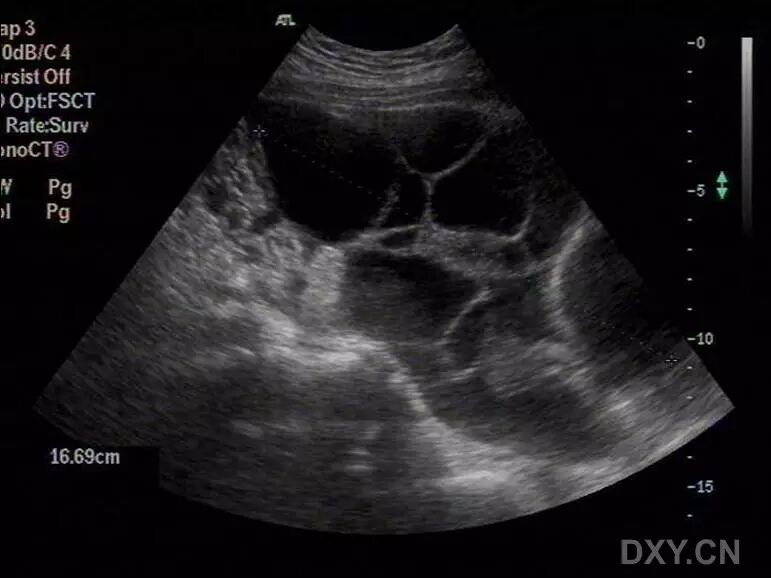

病例2(由丁香园注册用户「荷瓣111」提供):患者女,28岁,结婚5年未孕,应用促排卵药治疗2个月后,自觉腹部膨隆,呼吸困难。

超声所见如下图所示:

图1~3 显示子宫正常,盆腹腔可见两个相依的囊性肿物,其内见多条光带分隔,子宫被压在增大的卵巢下方

图4 显示肝肾区的腹腔积液